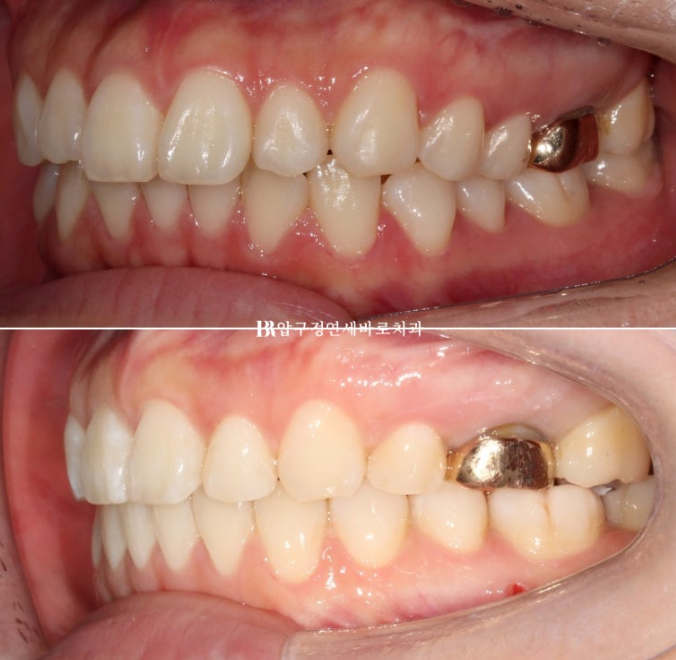

This patient came in June 2023 for protrusion and alignment improvement.

A mismatch in the midline is visible.

Because the upper front teeth protrude, the gap with the lower teeth is large.

If the front tooth bite is in this condition, the lips cannot close comfortably.

This can cause lip incompetence.

Now the midline is aligned,

and the molar bite is also good.

Improvement in the midline and overbite

As the upper front tooth protrusion was resolved, the gap between the upper and lower front teeth decreased.

With the protrusion resolved, the lips that could not close comfortably now close easily.

Lip incompetence was resolved.

The gummy smile was also resolved, and the absent buccal corridor was created.

One change that came with the buccal corridor is that the smile changed from a somewhat cramped look, where the gums and teeth seemed tightly packed when smiling, to a smaller and cleaner-looking smile.